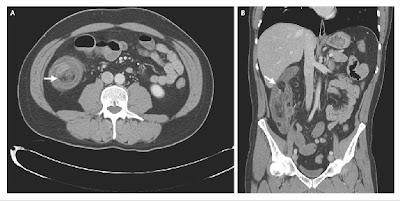

Physical examination showed moderate abdominal distention. Computed tomographic scans of his abdomen revealed an ileocecal intussusception (Panel A, arrow) with a pathologic mass, 2.5 cm in diameter, at the apex, also known as the lead point (Panel B, arrow). Diagnostic laparoscopy was performed, and the diagnosis of intussusception was confirmed.

Laparoscopically assisted ileocecal resection with primary anastomosis was performed. Gross inspection of the specimen showed a pedunculated lipoma within the terminal ileum. The patient had a rapid recovery, with complete resolution of his symptoms.